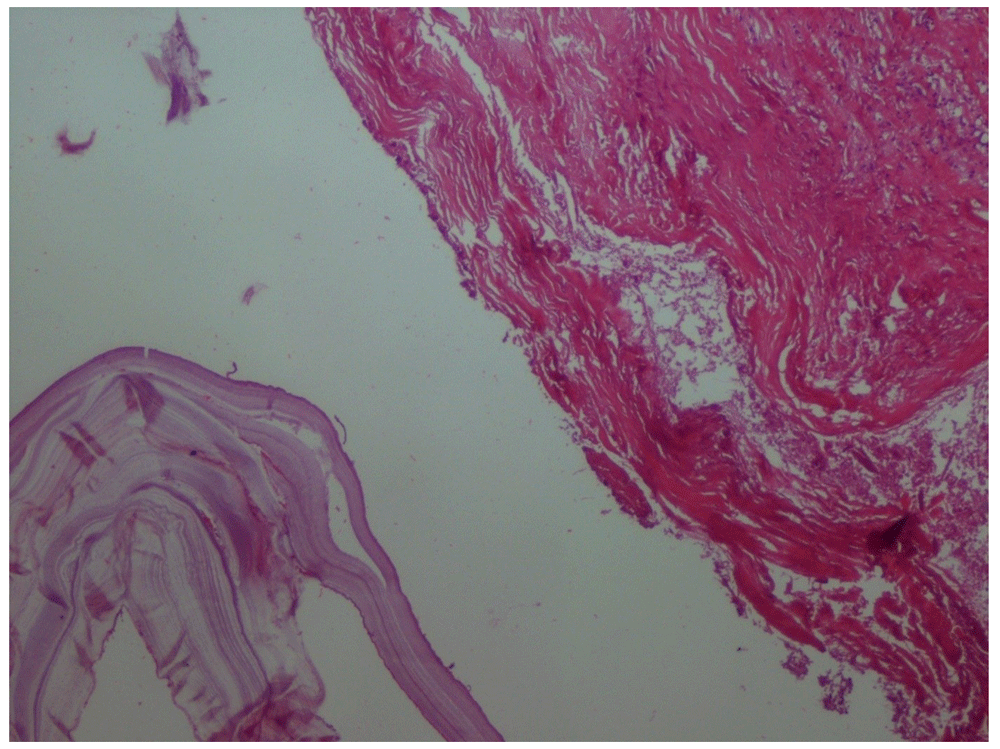

Microscopic examination using haematoxylin and eosin staining of paraffin sections of the cyst revealed classic layers of a hydatid cyst; pericyst (fibrous outer layer), ectocyst (laminated, hyaline and acellular middle layer) and endocyst (inner germinative layer) (Figure 3). This ascertained the diagnosis of hydatid disease.

Figure 3. Microscopic appearance of the cyst wall.

Haematoxylin and eosin, x40 magnification.